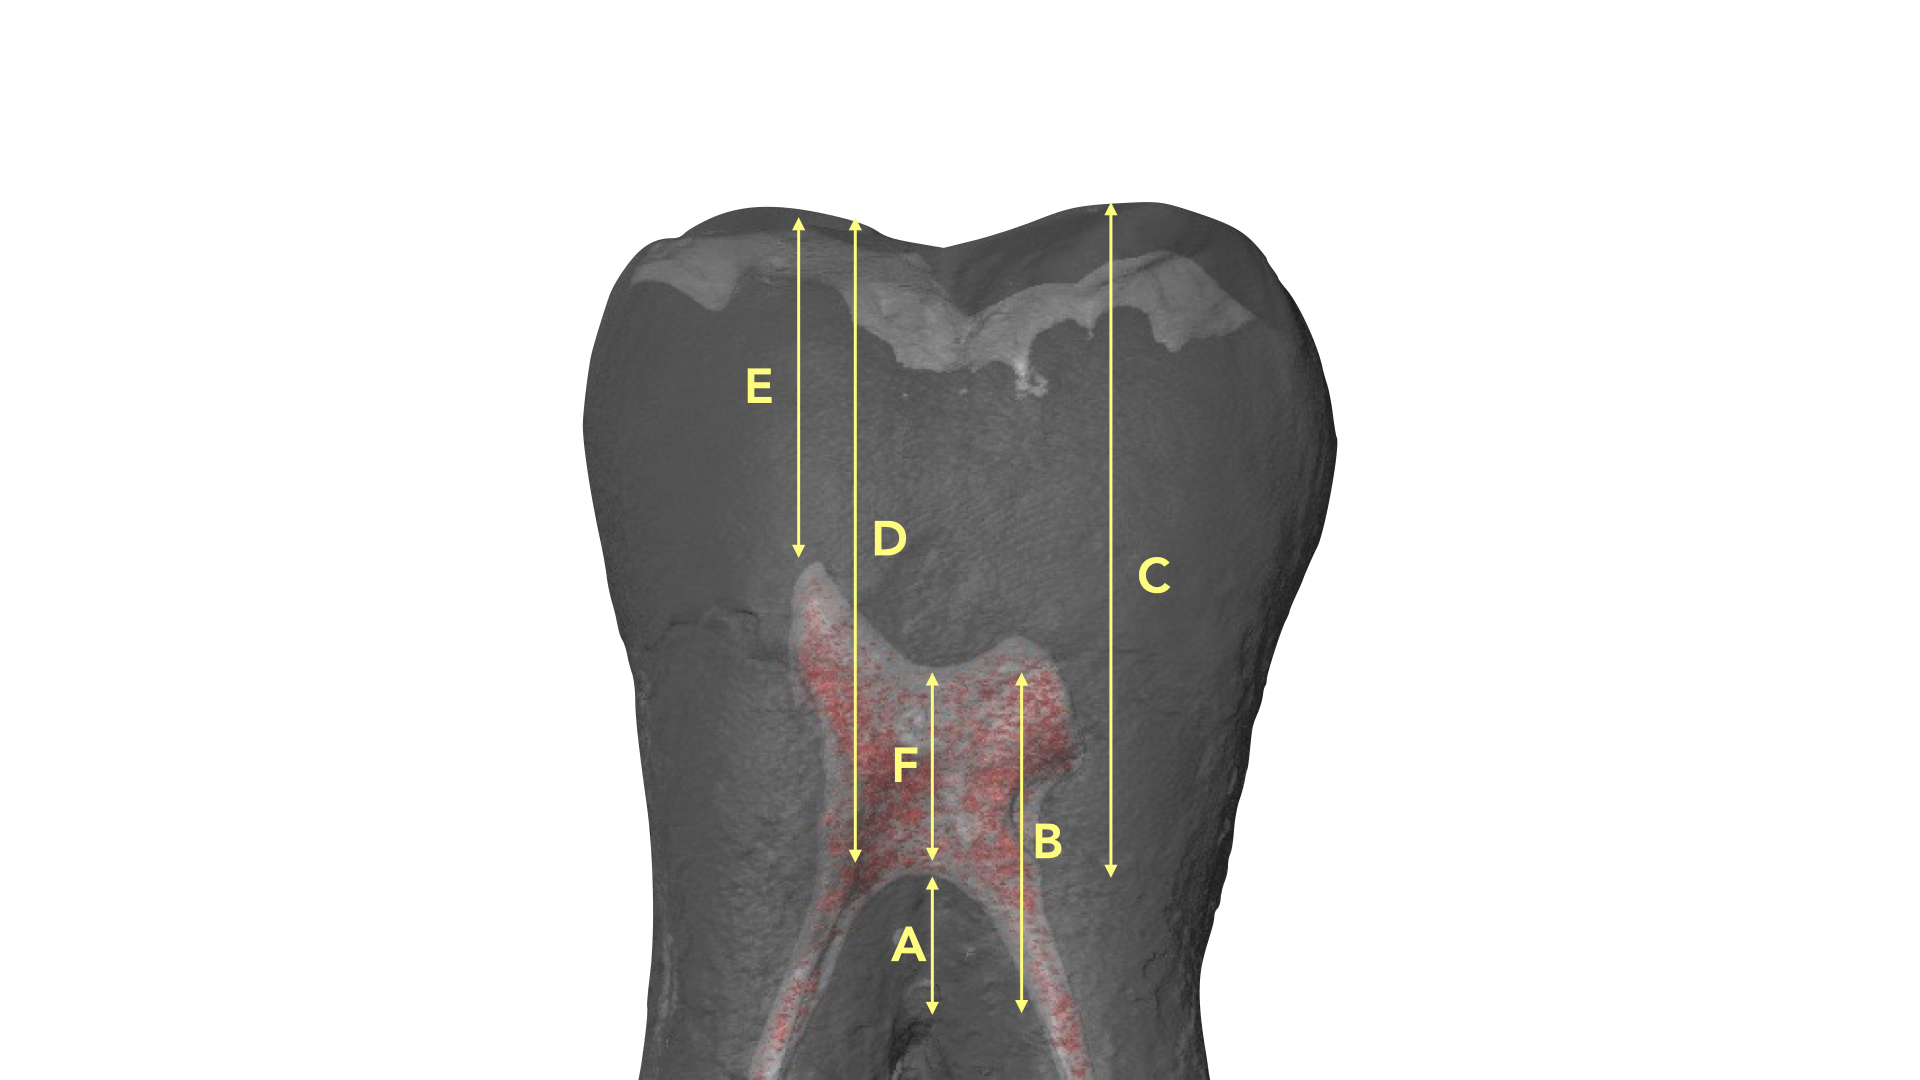

Deutsch8-9 ci fornisce delle misure morfologiche sulla relazione tra superficie occlusale, altezza, tetto e pavimento della camera nei pluriradicolati, GAC.

In questi elementi il tetto della camera pulpare si trova in corrispondenza della giunzione amelo cementizia.

Nei molari la distanza tra la sommità di qualsiasi cuspide e il tetto della camera pulpare è di circa 6,3 mm, nei premolari superiori è di 6,94 mm.

La camera pulpare ha un’altezza di circa 1,5-2 mm e la distanza media dal pavimento della camera alla forca è di 3 mm circa (Tabella 1) (Figura 13).

Queste regole, che sono poi state confermate da una più recente pubblicazione grazie all’analisi microCT dei campioni analizzati10, assumono un valore di notevole rilievo e forniscono all’operatore nozioni di base per evitare errori e approcciare in modo razionale e prevedibile ogni terapia canalare.